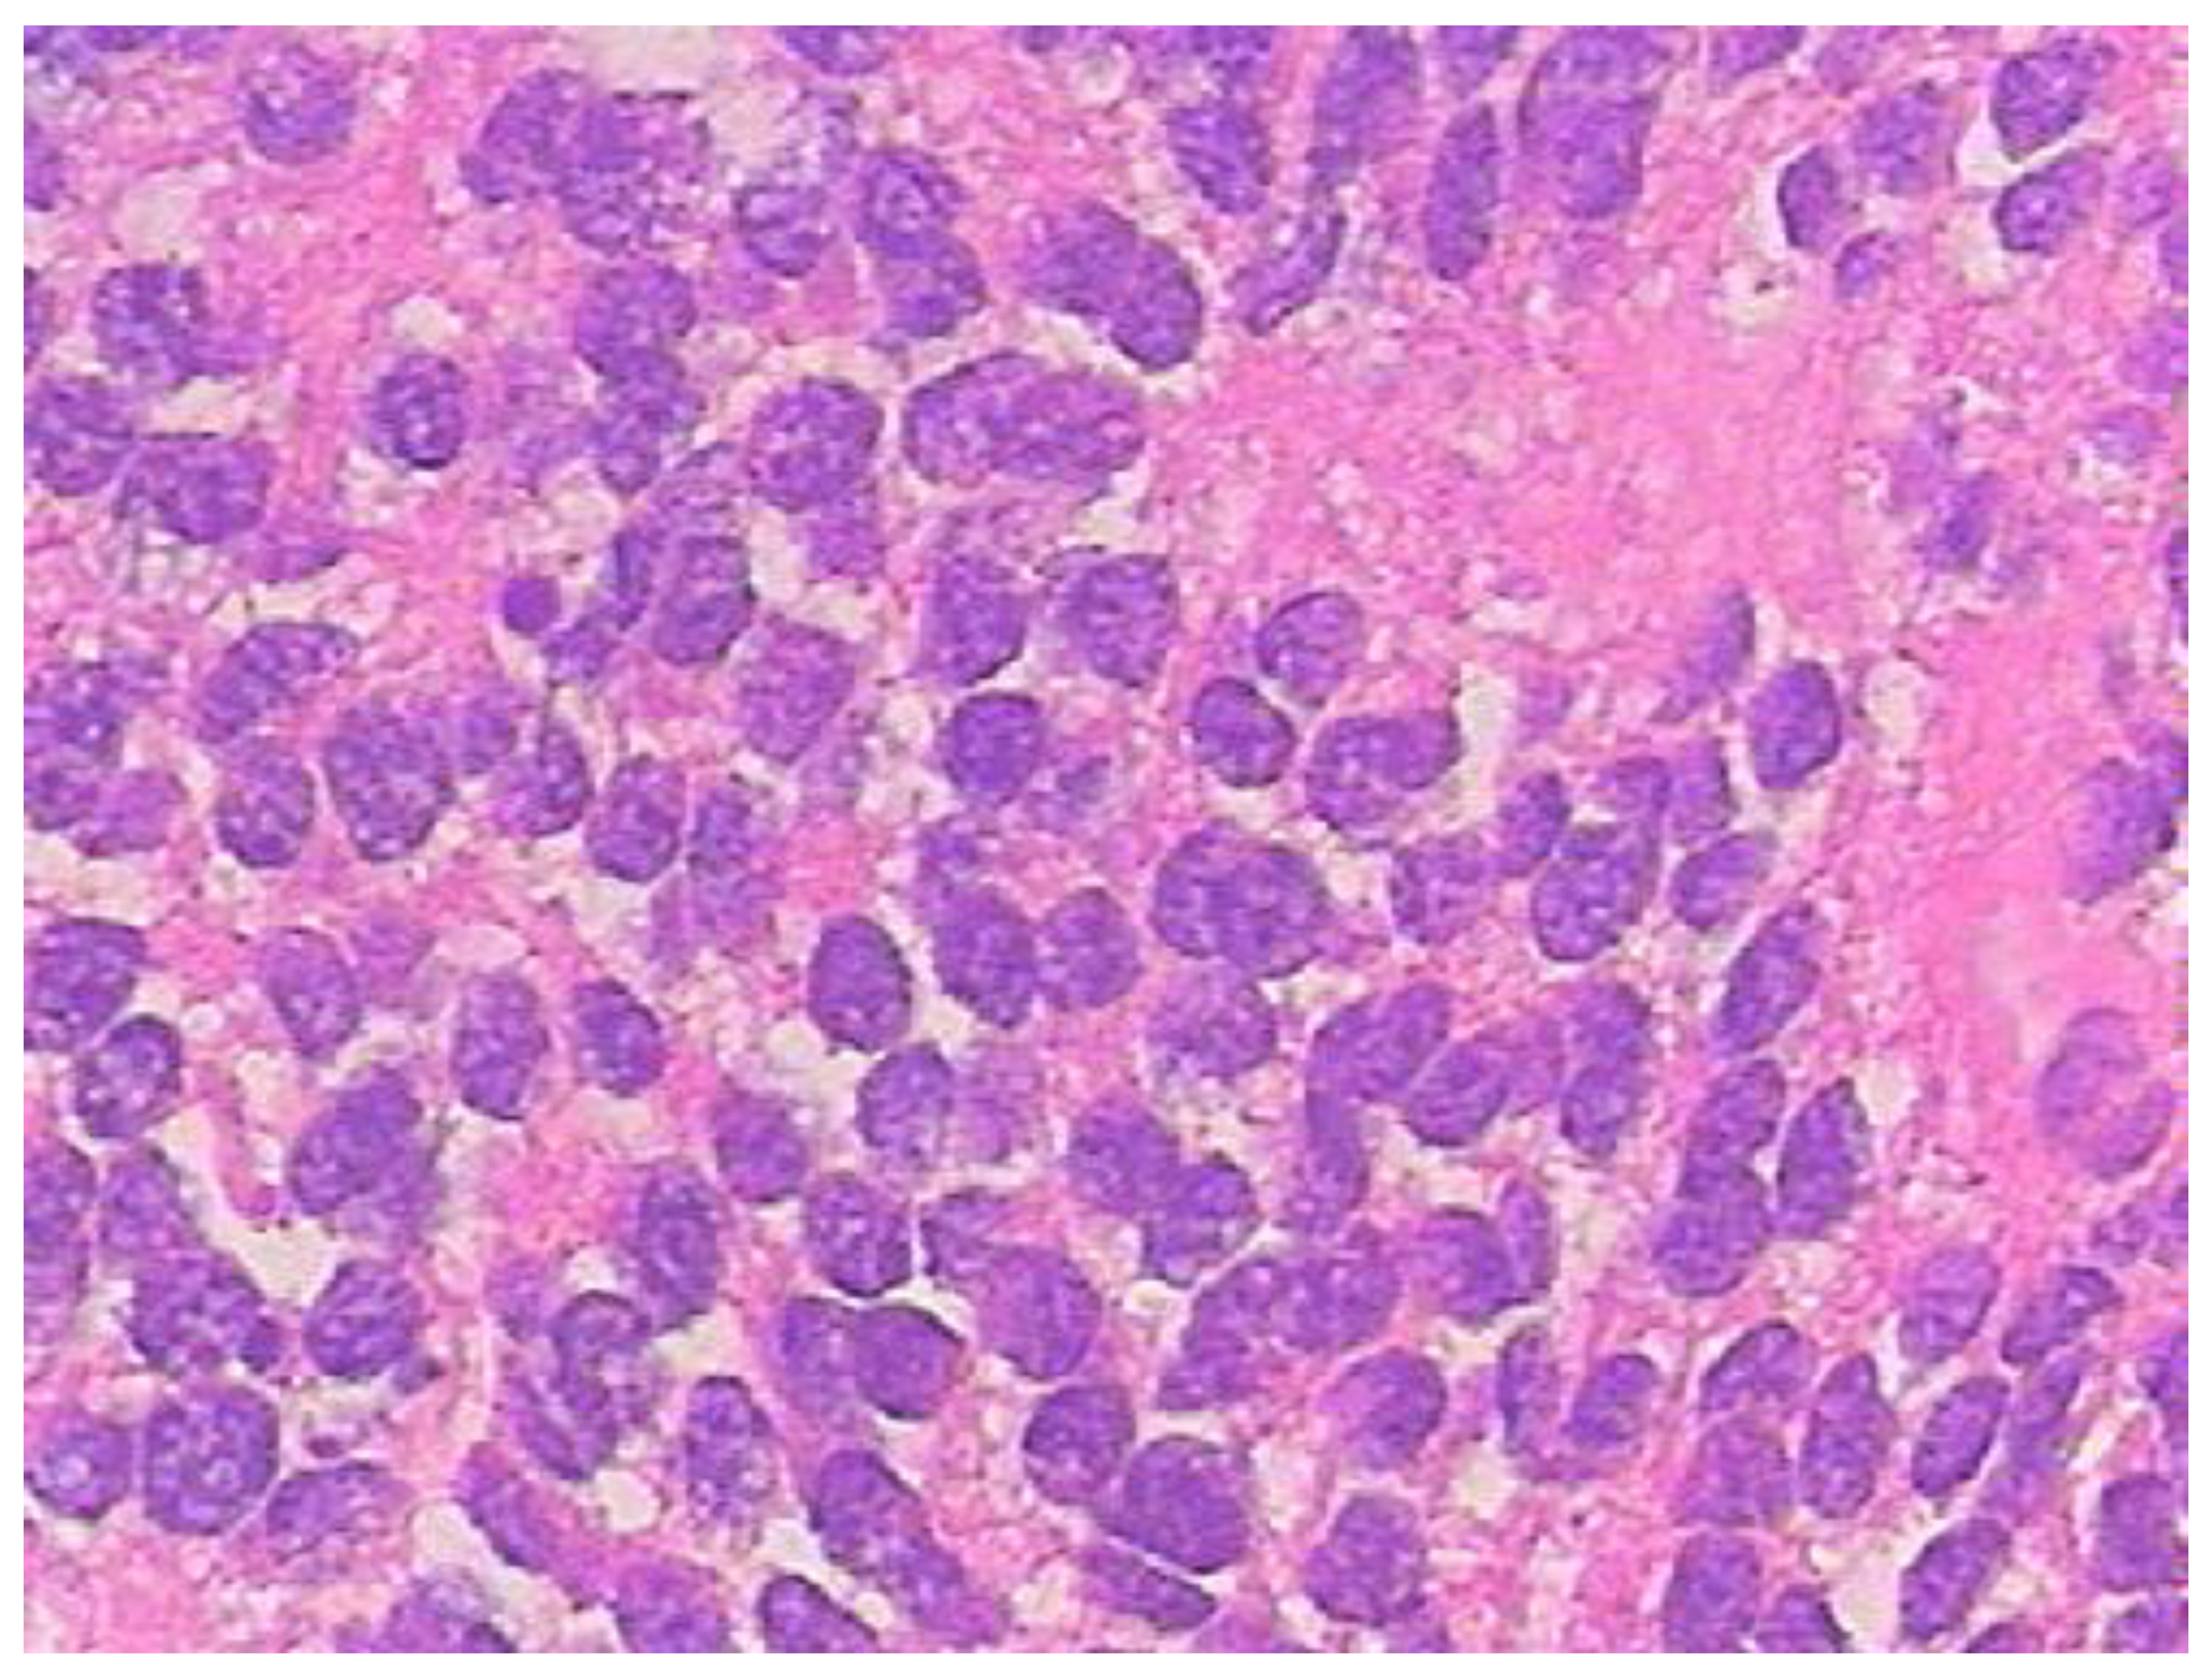

2. Case Presentation

3. Discussion